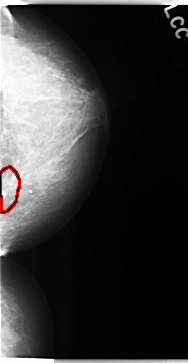

FILE: C_0107_1.RIGHT_CC.OVERLAY

TOTAL_ABNORMALITIES 1

ABNORMALITY 1

LESION_TYPE MASS SHAPE OVAL MARGINS ILL_DEFINED

ASSESSMENT 3

SUBTLETY 2

PATHOLOGY BENIGN

TOTAL_OUTLINES 1

BOUNDARY